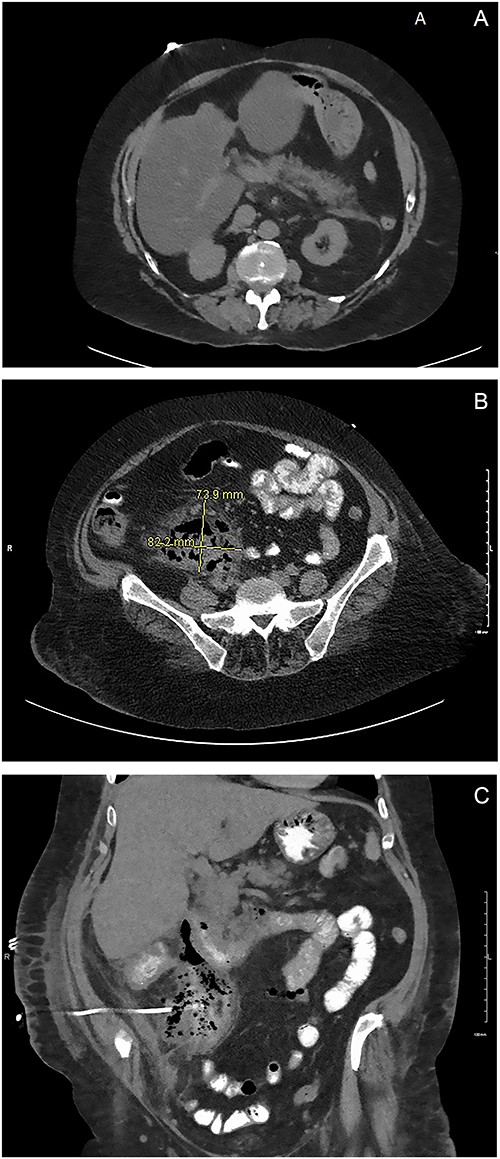

This case presents a 57-year-old female with a past medical history of nicotine dependence, and modified graham patch repair for perforated duodenal ulcer in 2013. She was admitted to the emergency department (ED) complaining of diffuse 10 out of 10 abdominal pain, associated with nausea, vomiting and hematochezia for 2 days. During the examination, it was observed that the patient’s vital signs were stable, and there was tenderness in the epigastric area, with no signs of peritonitis. A computed tomography (CT) scan in the ED showed fat stranding around the pancreas and fluid in the right retroperitoneum consistent with acute pancreatitis (Fig. 1). She was admitted for management of acute pancreatitis. Despite hospital management for 7 days, she continued to have worsening sepsis and blood culture grew anaerobic gram-negative rods.

(A) ED CT scan demonstrating fat stranding around the pancreas. (B) Large fluid collection in the retroperitoneum. (C) Oral contrast noted in the IR drain. Large fluid collection in the retroperitoneum consistent with duodenal perforation.

On hospital day six, general surgery was consulted for evaluation of anemia, with a hemoglobin declining to 6.6. She was given two units of packed RBC and scheduled for upper endoscopy (EGD). The EGD was done on hospital day 10, demonstrating one duodenal ulcer in the first portion of the duodenum. The ulcer was not actively bleeding and showed no signs of inflammation or fistula in the stomach or duodenal. The following day, the patient continued to have worsening leukocytosis. A subsequent CT of the abdomen and pelvis with oral contrast showed a 7 cm × 8 cm multiloculated fluid collection in the retroperitoneum extending from the duodenum to the pelvis. Additionally, a small amount of contrast extravasation was visible around the duodenum consistent with a duodenal perforation in the second or third portion (Fig. 1B). On examination, vital signs were stable, and the abdominal exam was benign. Due to the patient being stable, we elected to proceed with non-operative management. The IR team attempted to drain the fluid collection without success and patient remained septic. A CT abdomen and pelvis with oral contrast was obtained three days later showed a persistent retroperitoneal abscess extending from the level of the duodenum into the upper pelvis. There was evidence of a novel fistulous communication between the abscess and the posterior wall of the descending duodenum suggestive of a perforated duodenal ulcer. Additionally, diffuse wall thickening of the cecum and ascending colon was observed, accompanied by peri-colonic and peri-abscess fat stranding in the surrounding area (Fig. 1C). At this point, surgical exploration was then recommended as a course of action.